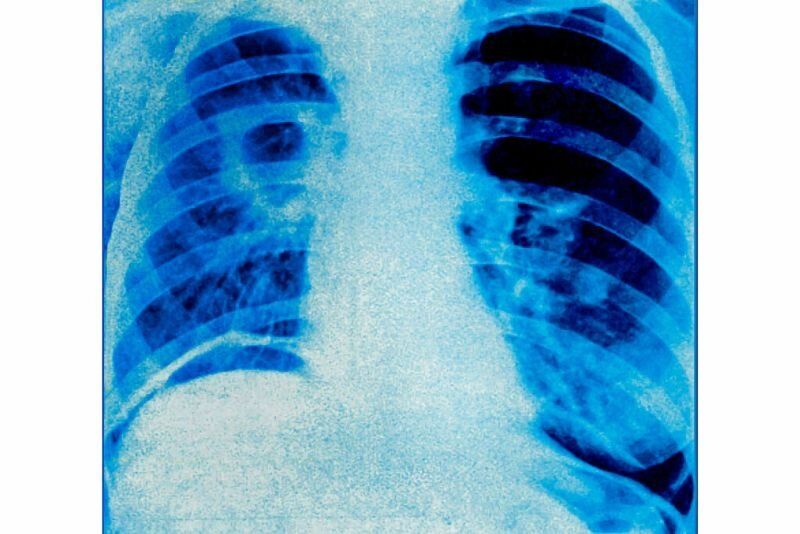

Туберкулозата се разпространява по въздушен път, когато болни от белодробна туберкулоза кихат или кашлят. За заразяването е достатъчно вдишване само на няколко микроба. Туберкулозата е предотвратима и лечима, допълниха от здравното министерство.

По данни на Световната здравна организация от 2000 г. досега 79 млн. души са излекувани от туберкулоза. През 2023 г. в световен мащаб близо 10,8 милиона души са се разболели от туберкулоза. Болестта засяга най-вече възрастните в най-продуктивните им години, но въпреки това, всички възрастови групи са изложени на риск.